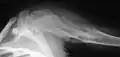

X-ray showing enchondromas localized in the humerus of a 37-year-old patient affected with Ollier disease -

Enchondromas localized in the upper part of the humerus of the same patient